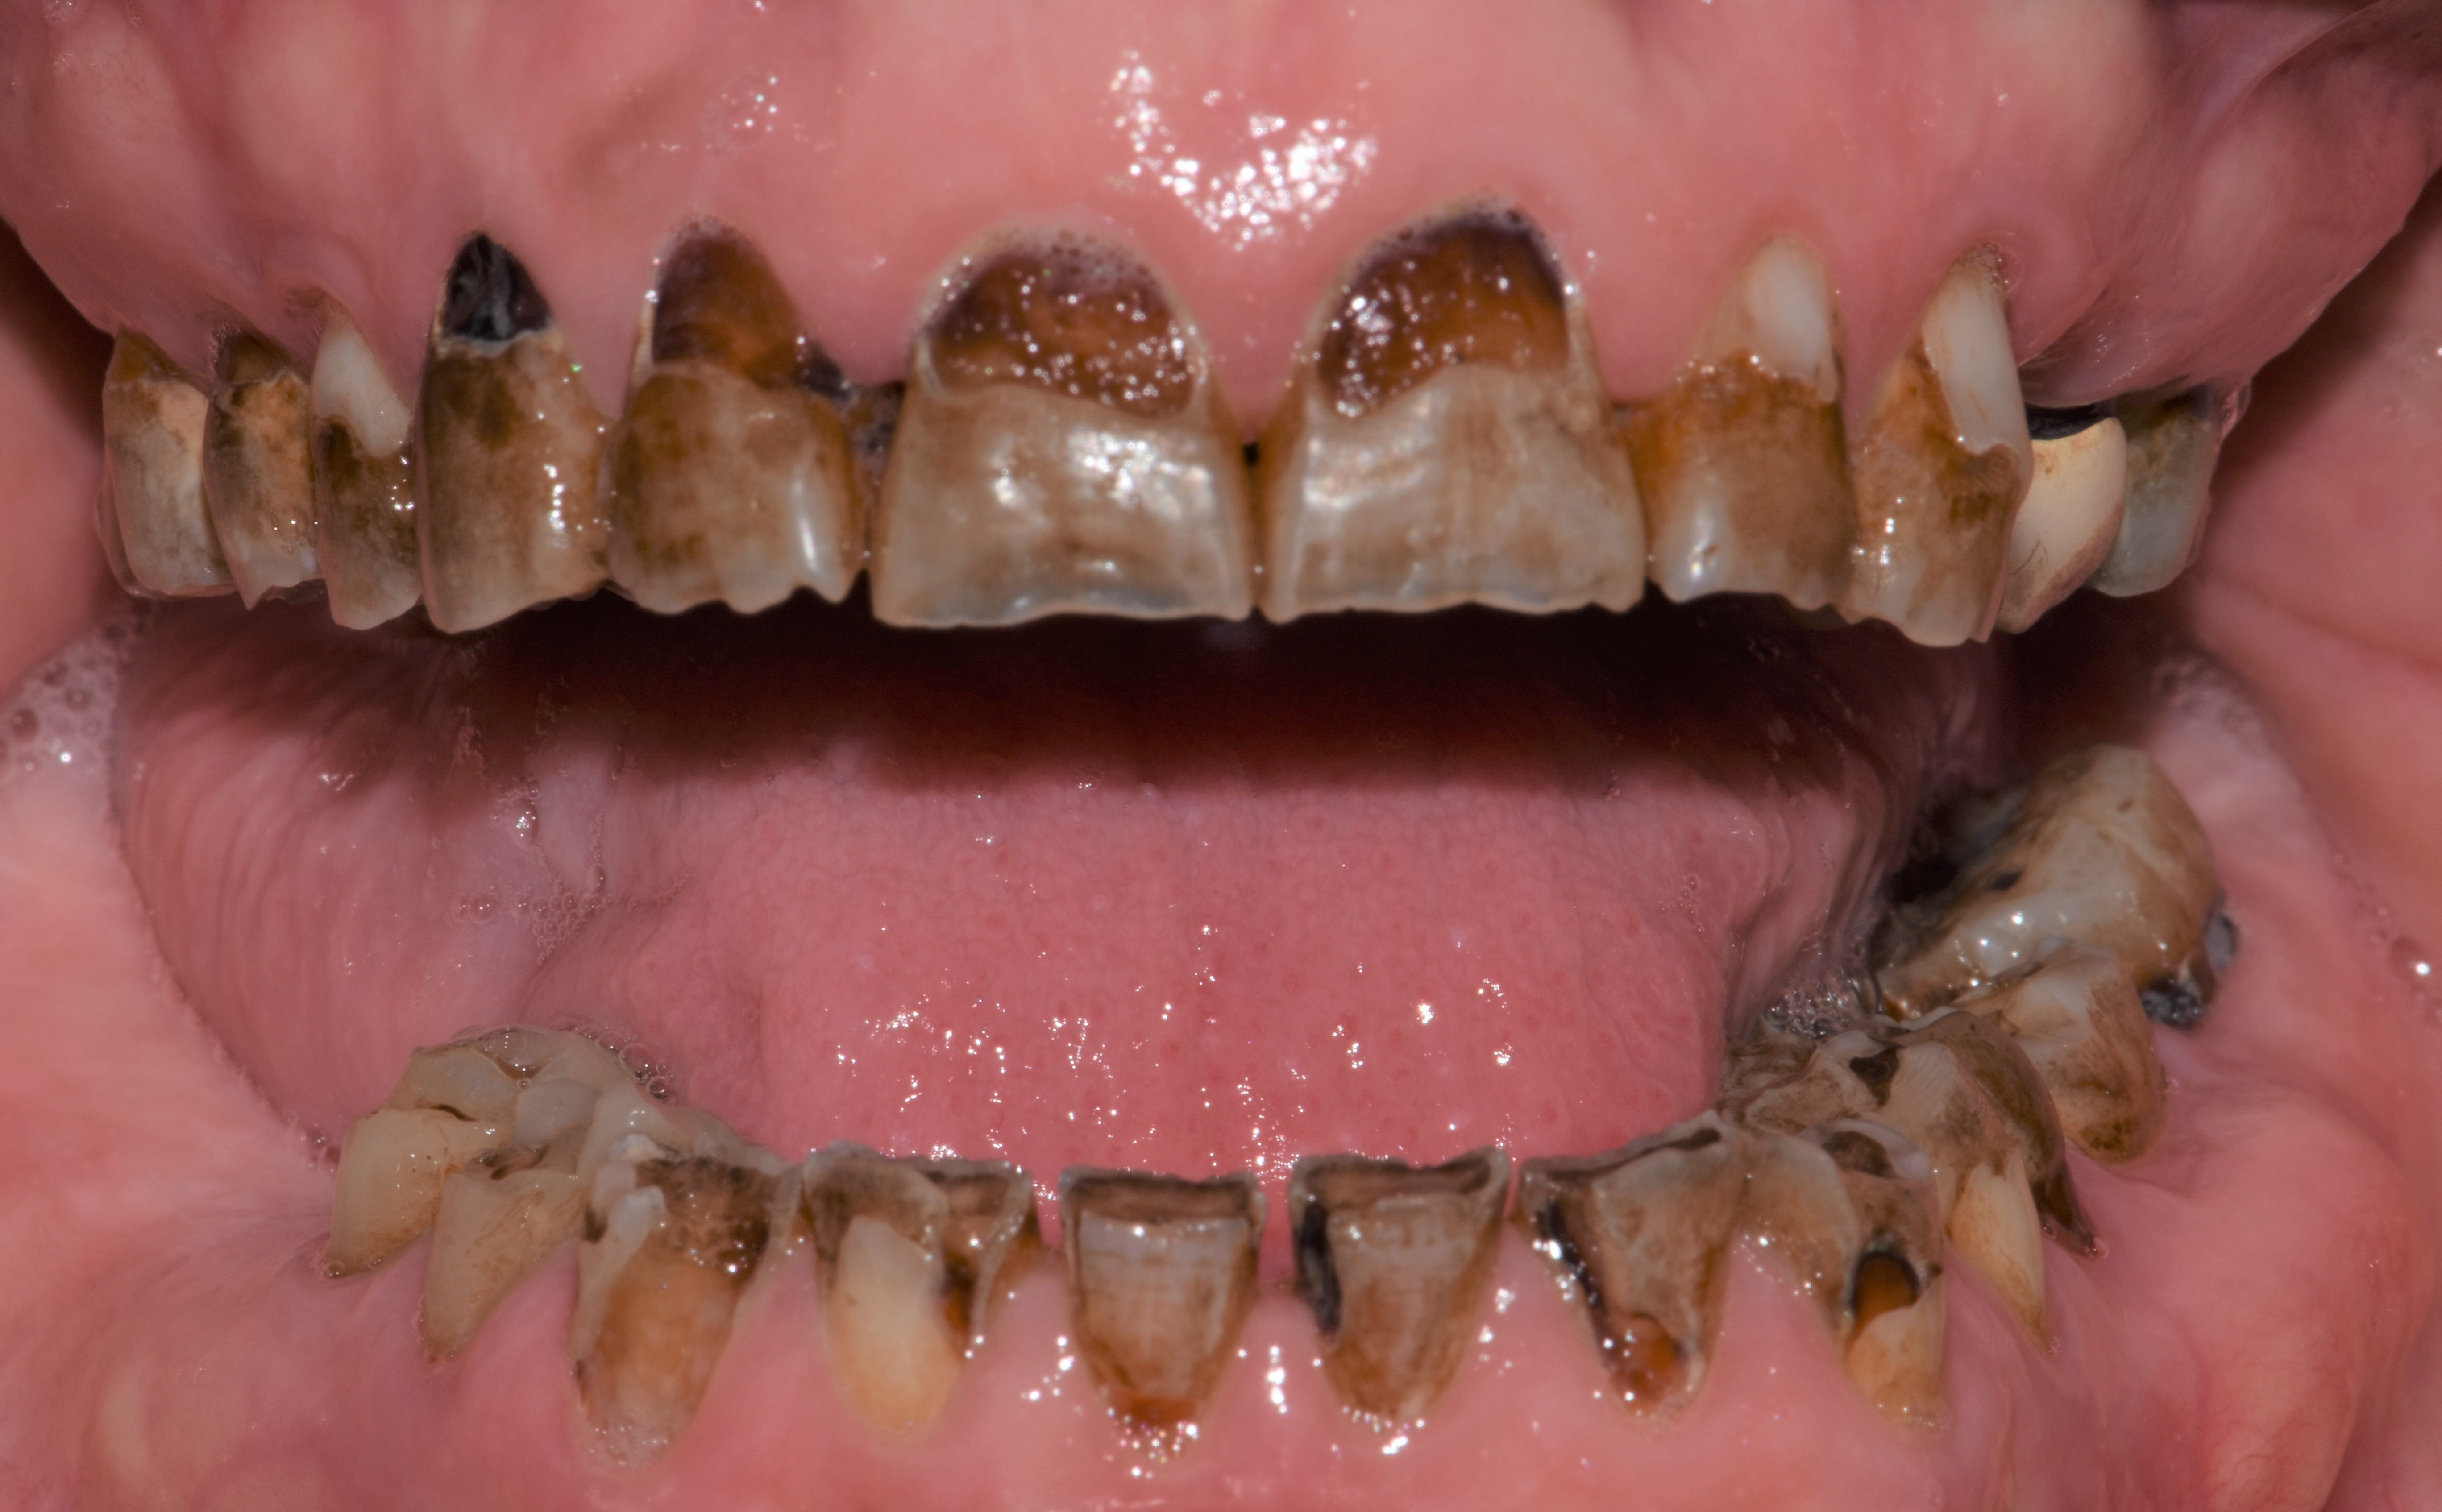

At a clinic treating patients in an underserved population, a 54-year-old female patient presented requesting extraction of all of her teeth and fabrication of dentures for her long-term restorations. The patient had a history of breast cancer, which had been treated with chemotherapy. She believed that full dentures would be an appropriate treatment option for her, owing to the poor state of her oral health and dentition and because she had limited financial resources and did not think that she could afford restoration of her teeth. The patient reported that she had experienced depression and alcohol abuse because of her cancer diagnosis, and that she had neglected her dental care during the course of her cancer treatment, resulting in generalized moderate-to-severe caries with moderate wear due to bruxism (Figure 1 through Figure 5). She also presented with significant staining of her remaining dentition due to the alcohol abuse.

Fig. 2